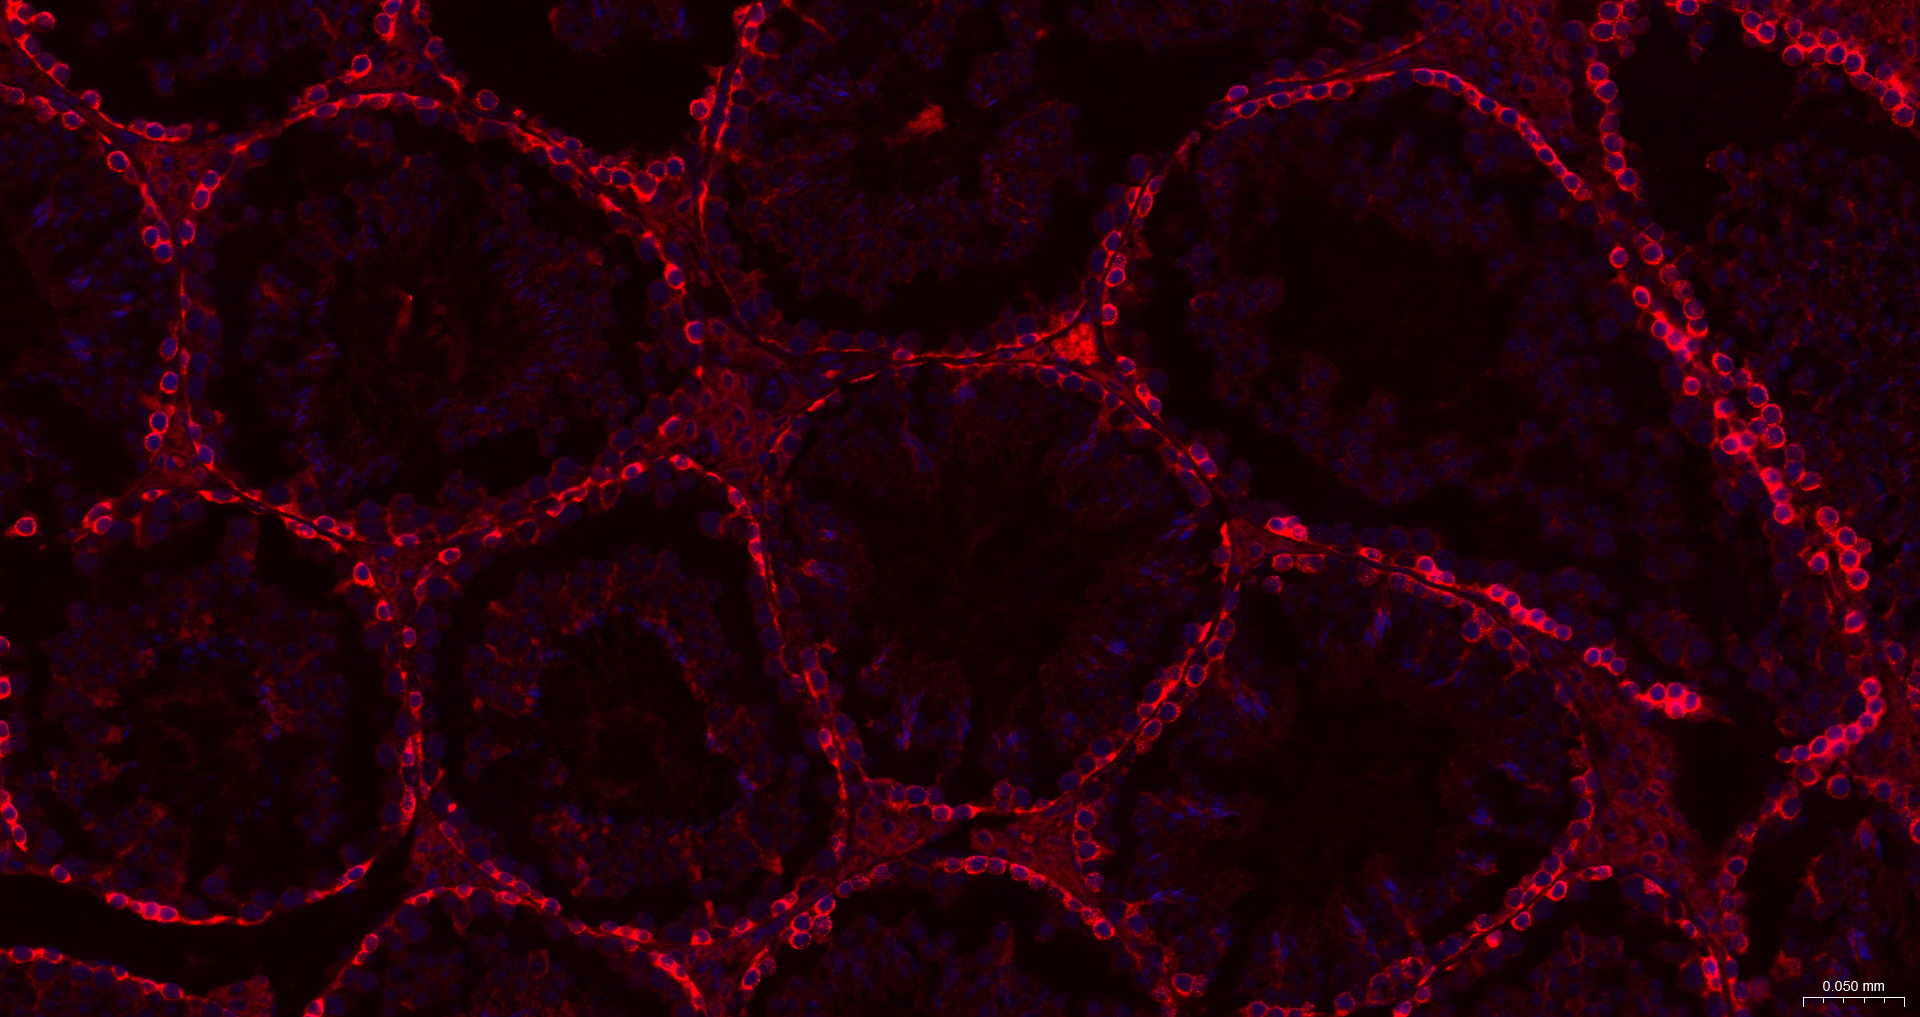

IF(IHC-P) IFIHC-P1:100-500